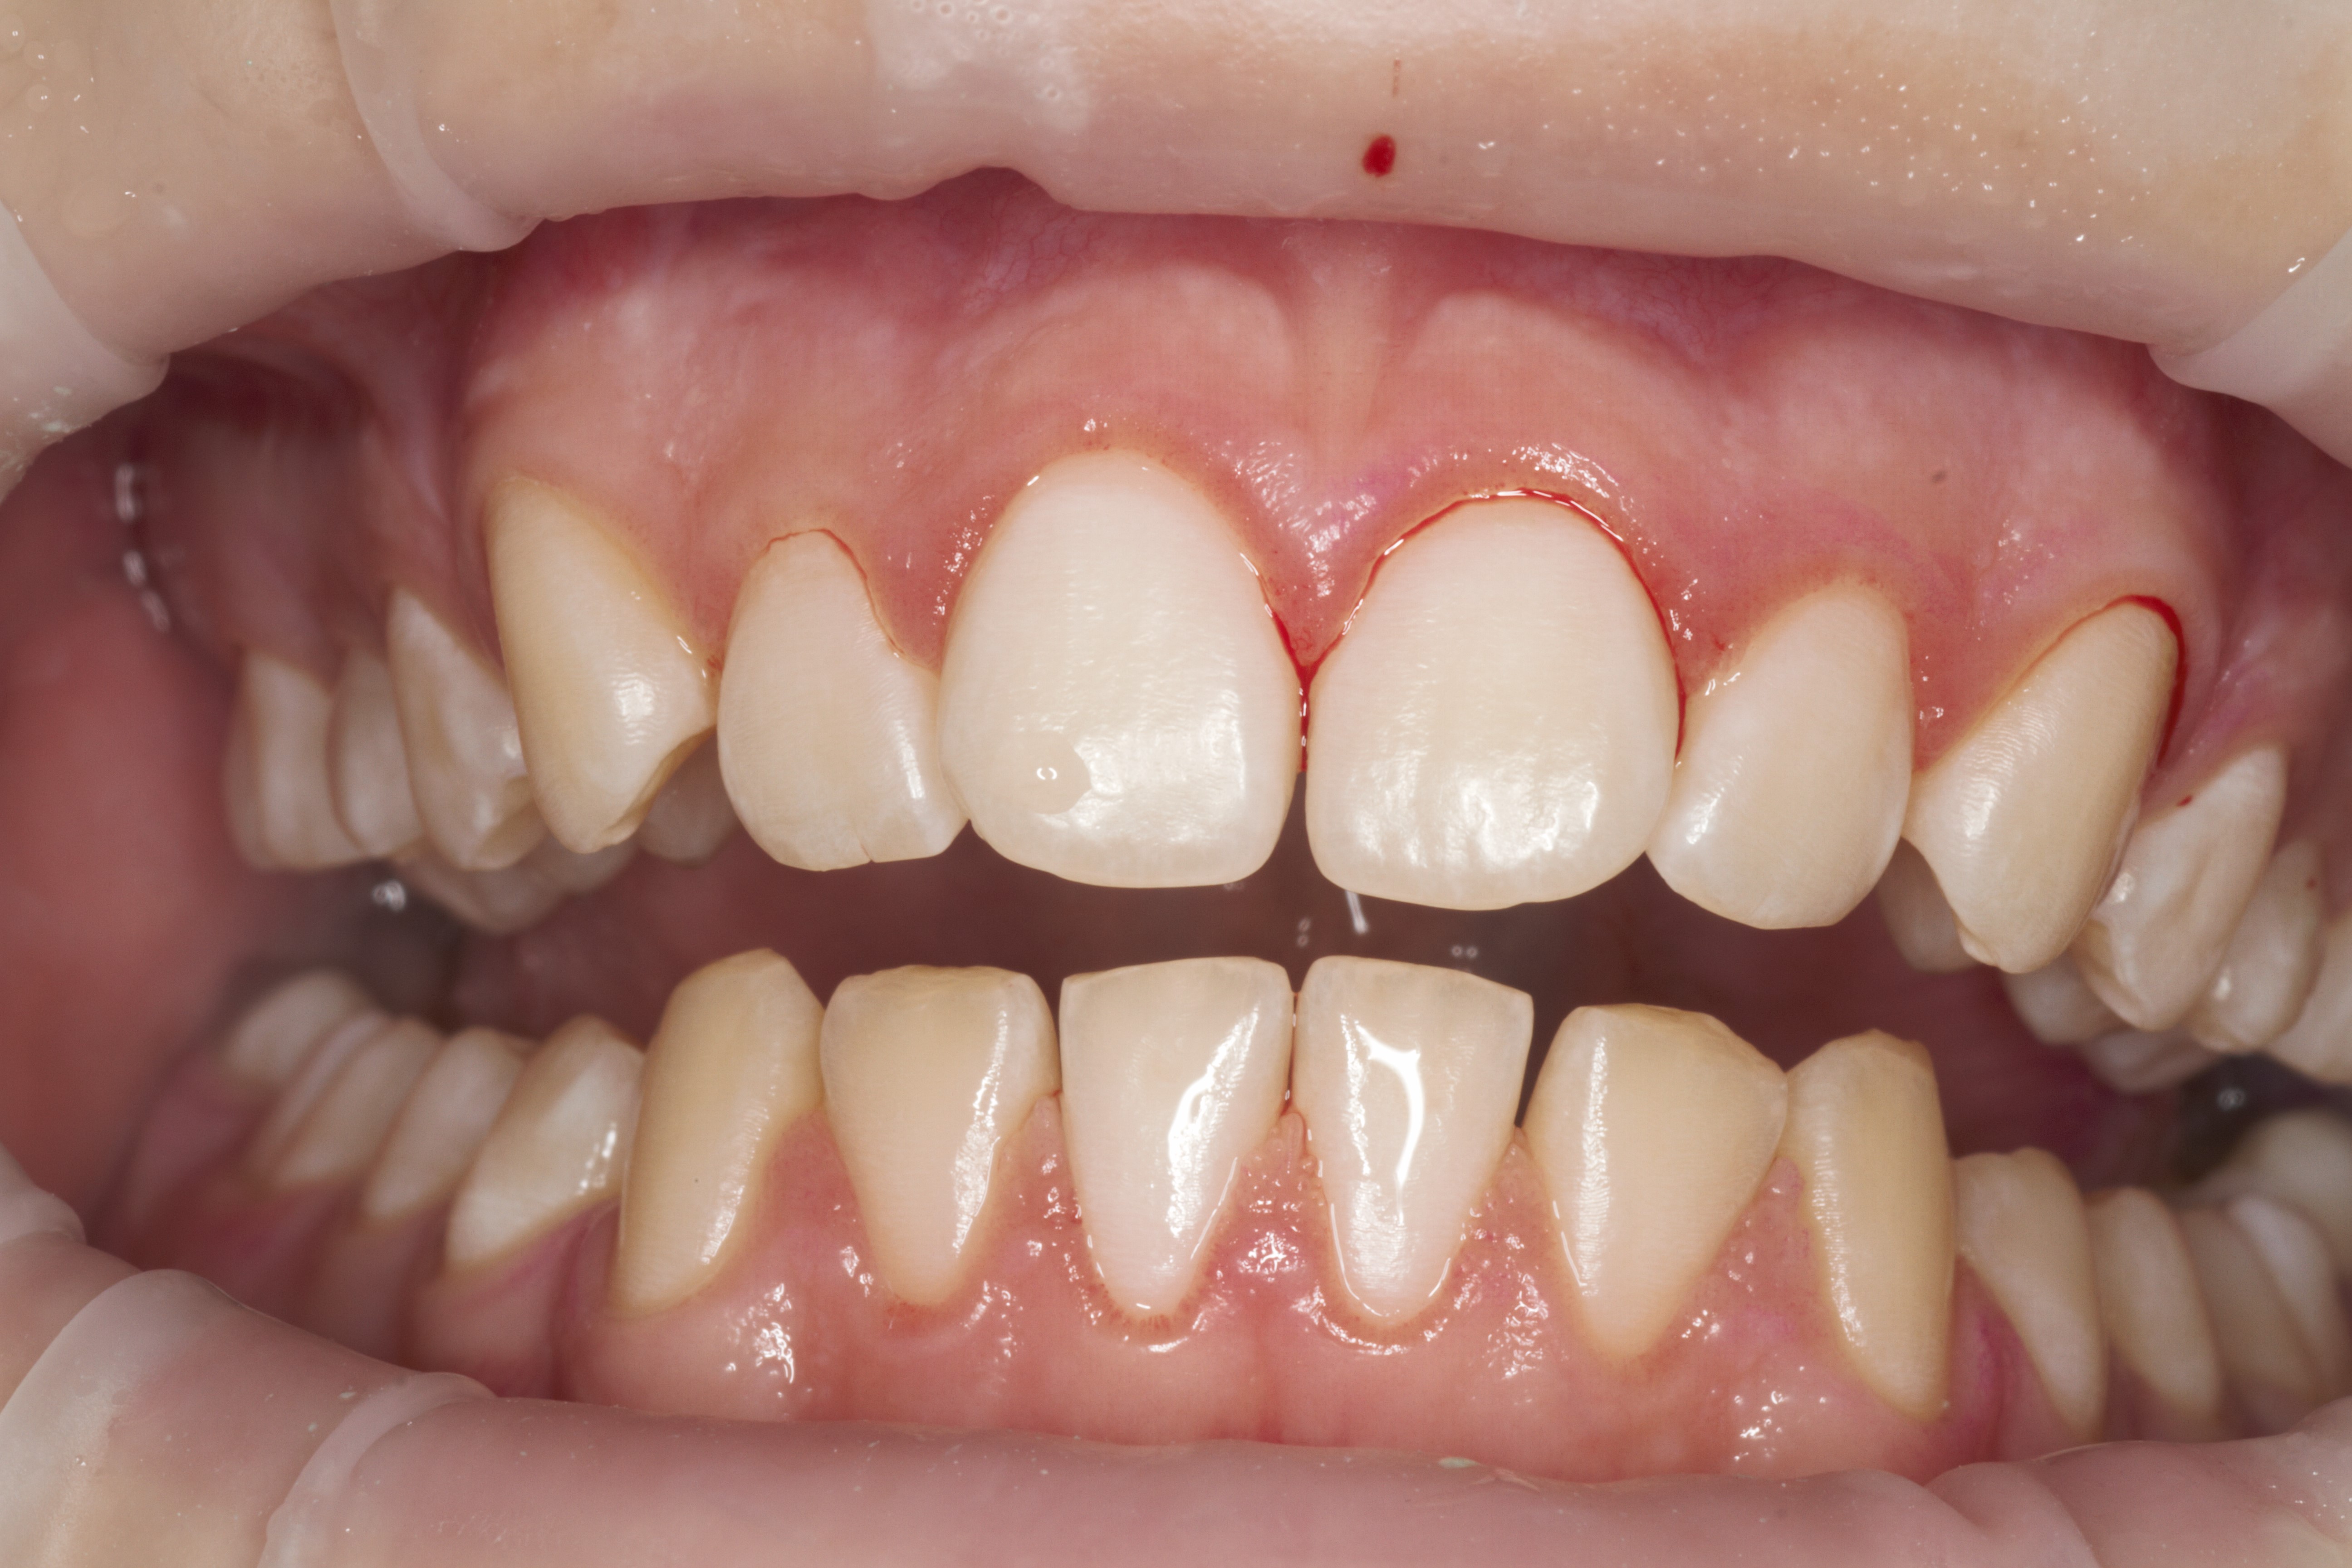

- Проведение профессиональной гигиены полости рта по GBT-протоколу на аппарате AIRFLOW® PROPHYLAXIS MASTER

- Эстетическая реставрации жевательной и фронтальной группы зубов современными пломбировочными материалами, диагностика кариеса на ранних этапах развития, предупреждение образования вторичного кариеса в области запломбированных зубов